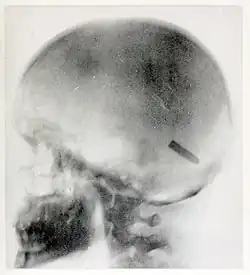

On August 20, 1899, she took one of her most famous radiographs, an image showing a Mauser 7 mm bullet lodged in the brain of John Gretzer Jr., in the region of the left occipital lobe.[12][15] Private Gretzer, of the 1st Nebraska Volunteers, wounded at Mariboa, Philippines on 27 March 1899 during the Spanish–American War. The private later returned to duty as a mail clerk.[16] Accounts of the case were reported in the 1902 edition of The International Text-Book of Surgery and in newspapers.[17] Another case of a bullet lodged in a soldier's skull, X-rayed by Fleischman was also reported in newspapers in 1899.[18]